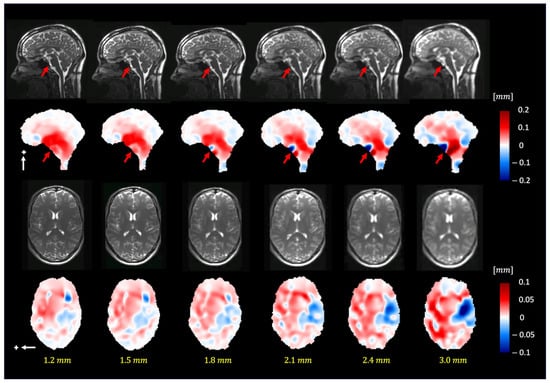

Figure 7 depicts the extracted motion field by 3D q-aMRI (Supplemental Video S6) for different isotropic voxel sizes (1.2–3.0 mm3). The extracted motion field remains consistent up to an isotropic voxel size of 1.8 mm. The red arrows in the sagittal plane point to the basal artery (Supplemental Video S7), which exhibits apparent motion (larger than 1.5 pixels) and, based on the phantom simulations, will result in an error in the estimated motion field.

Figure 7. The pulsatile brain motion in the sagittal (S/I direction, indicated by a white arrow) and axial (L/R direction, indicated by a white arrow) directions for different isotropic spatial resolutions. Plus sign represent the positive direction of motion. As can be seen, the algorithm can robustly estimate the motion field for different image resolutions (up to 1.8 mm isotropic voxel size). Note that the dark blue/red regions (red arrows) in the sagittal plane point to the basilar artery, which exhibits apparent motion (larger than 1.5 pixels).